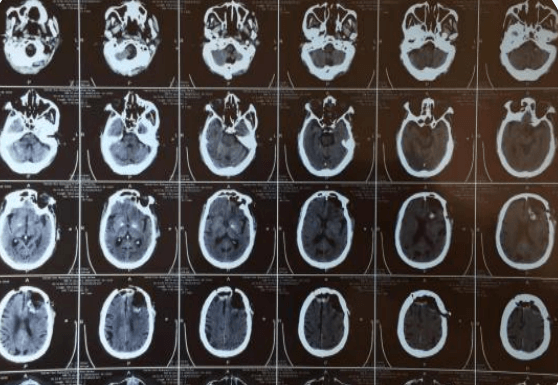

約3個(gè)月前,趙大爺在我院查顱腦CT示:左側(cè)額顳部占位,多考慮腦膜瘤;右側(cè)額部皮下脂肪瘤,當(dāng)時(shí)患者無(wú)明顯癥狀,選擇保守治療,約一周前,患者出現(xiàn)意識(shí)混亂,頭悶表現(xiàn),家屬為求進(jìn)一步治療,解決患者不適,提高患者生活質(zhì)量,入院治療。在劉小雷主任和游文良副主任醫(yī)師的指導(dǎo)下,經(jīng)過(guò)醫(yī)護(hù)一體化協(xié)作模式的共同努力,為78歲高齡的趙大爺術(shù)前制定精準(zhǔn)的手術(shù)方案,術(shù)中在病人家屬的許可下,實(shí)施顯微鏡下顱內(nèi)腫瘤切除術(shù),經(jīng)過(guò)精細(xì)的手術(shù)操作,手術(shù)順利完成,并且一并切除右側(cè)頭皮脂肪瘤,顱內(nèi)外問(wèn)題一起解決,護(hù)理團(tuán)隊(duì)根據(jù)患者病情特點(diǎn)制定了護(hù)理計(jì)劃及護(hù)理措施,密切觀察患者瞳孔意識(shí)變化,肢體活動(dòng)情況,觀察患者生命體征變化,二十四小時(shí)出入量是否平衡,并詳細(xì)的記錄各項(xiàng)指標(biāo)的變化,在護(hù)士專(zhuān)業(yè)而細(xì)致地看護(hù)下,術(shù)后五天,患者無(wú)任何不良反應(yīng),恢復(fù)良好,身體各項(xiàng)指標(biāo)一切正常,無(wú)后遺癥。在神經(jīng)外科二病區(qū)醫(yī)護(hù)團(tuán)隊(duì)的精心治療和護(hù)理下,趙大爺病情日見(jiàn)好轉(zhuǎn),家屬臉上也露出了久違的笑容。